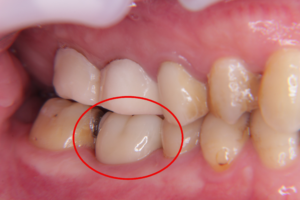

右下6番目の歯が残せないので抜歯となり、インプラント希望の患者様です。

こちらが埋入前、埋入後のCTレントゲンです。

埋入前

埋入後

赤い丸がある箇所に、当日、正しい位置へインプラントが埋入され、仮歯まで入りました。